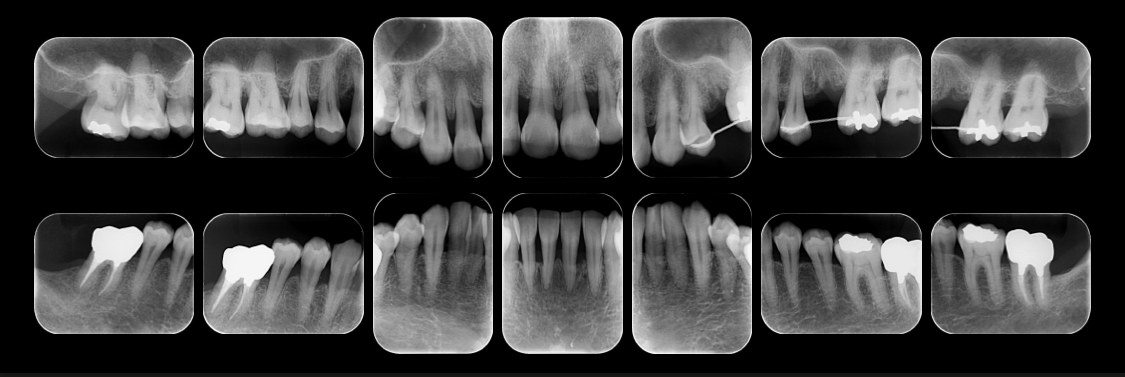

治療例

重度歯周病の症例